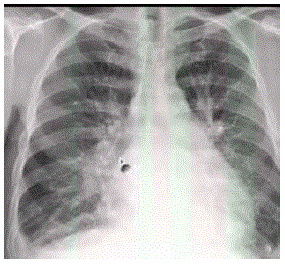

Homem, 56 anos, admitido na emergência por quadro de dispneia há 5 dias, com piora progressiva, evoluindo com tosse seca e ortopneia. Na admissão, se apresenta dispneico, com estertores em 2/3 inferiores de tórax e extremidades frias. PA: 150 x 70mmHg FC: 100. Nega febre ou expectoração. Sem histórico prévio de doença cardíaca. Não faz uso de medicações. Radiografia de tórax abaixo.

Qual a conduta inicial?